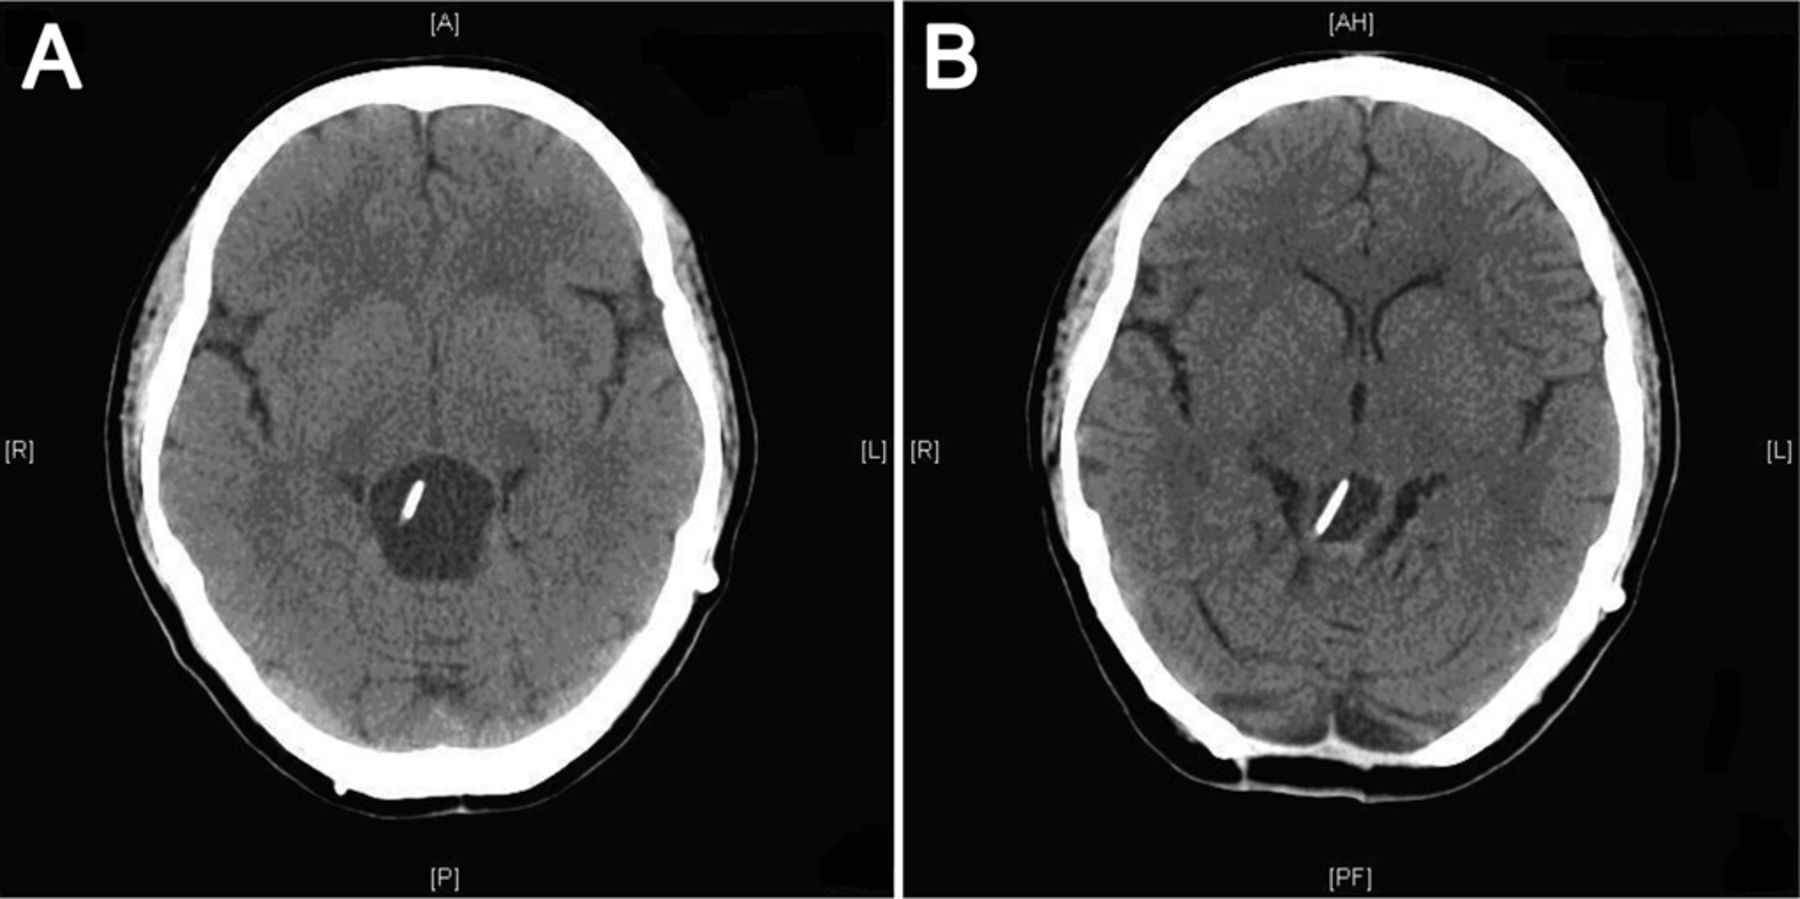

第一个调查(一个完整的床边临床检查之后)是一个41头部的CT扫描来评估已知的松果体囊肿,水库和分流安置和任何其他颅内病变。MRI能产生更高的分辨率的图像,但可能不会立即可用。她松果体区囊肿,CT扫描显示显著的递增规模相比一年前她最后的成像研究。颅内Rickham水库导管内原位囊肿(图1一个)。导管改为脑室-腹腔分流术也在位置和没有脑积水。经皮囊肿通过Rickham水库的愿望是未遂,总共20毫升淡稻草色的羊水持续产生。她双边听力显著改善和向上共轭凝视麻痹囊肿愿望后完全解决。重复CT扫描显示显著减少松果体区囊肿的大小(图1 b)。核磁共振大脑扫描显示松果体区囊肿与厚增强墙压缩对中脑和后第三脑室。吸气液被送细胞学检查,返回对恶性肿瘤细胞不利。